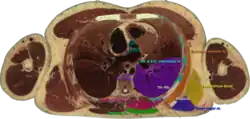

![]() Cross section #1428 of the Visible Human Male showing the structures of the triangle of auscultation | |